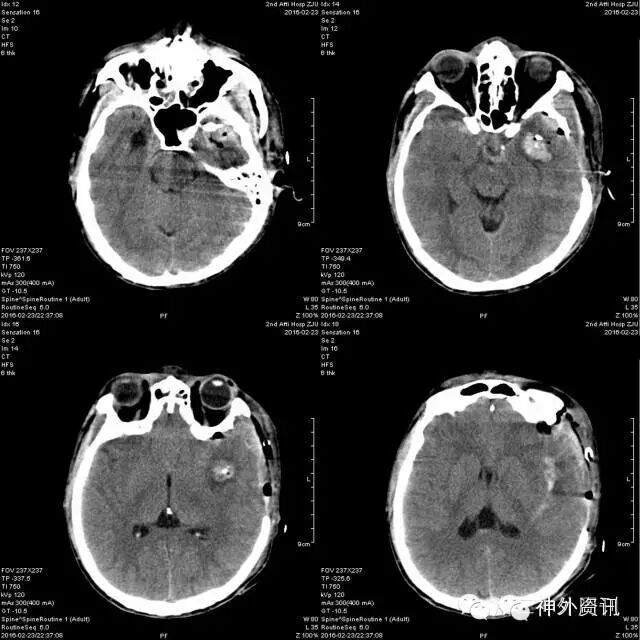

头颅CT提示:可见金属棒状物自右颈部颌下斜行经口咽、左侧鼻咽及中颅底,至左侧额颞部颅骨穿出,伴右侧颌下及上颈部皮下气肿,周边放射状伪影明显,周围结构显示欠清,左颞叶脑实质穿透,异物周边脑实质水肿,右侧脑室受压变形,局部中线结构轻度右偏。左顶部头皮软组织肿胀。左侧中颅底及左顶骨骨折,鼻骨骨折(见图2)。

随后,由耳鼻喉及口腔科医师处理鼻咽部及口咽部伤口。术后患者病情平稳,神志转清,次日复查CT提示:颅内异物取出术后,术区少量积血、积气(图7)。术后第2天转普通病房继续抗感染等治疗。

图7. 术后复查头颅CT。